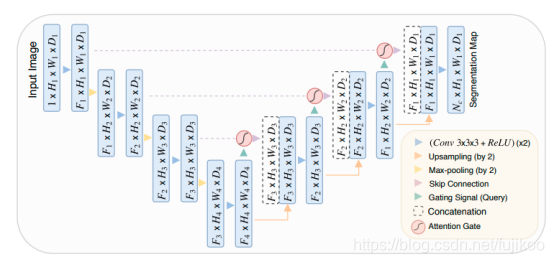

AG接在每个skip connection的末端,对提取的feature实现attention机制。结构如图:

可以从上图看出:Attention-Unet和U-net的区别就在于decoder时,从encoder提取的部分进行了Attention Gate再进行decoder。